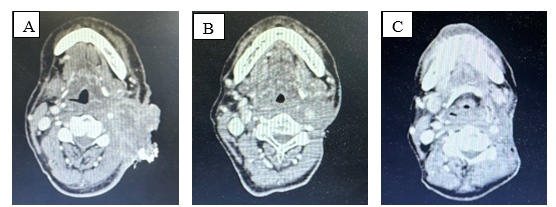

Bệnh nhân được chụp cắt lớp vi tính vùng hàm mặt:  Tại vị trí dưới hàm trái có khối tổ chức kích thước 71x60mm xâm lấn khoang cảnh, xâm lấn khoang cạnh hầu bên trái, không rõ ranh giới với tuyến mang tai trái, xâm lấn rộng da và tổ chức dưới da gây sùi loét rộng.

Hình 2. Khối dưới hàm trái xâm lấn rộng tương ứng tổn thương ác tính tái phát

Trên hình ảnh cắt lớp vi tính: sau 6 chu kỳ điều trị, kích thước khối u giảm từ 71x60mm (trước điều trị) xuống 32x25mm, đánh giá bệnh đáp ứng một phần theo tiêu chuẩn RECIST 1.1

Hình 5. A. Trước điều trị; B. Sau 3 chu kì điều trị; C. Sau 6 chu kì điều trị